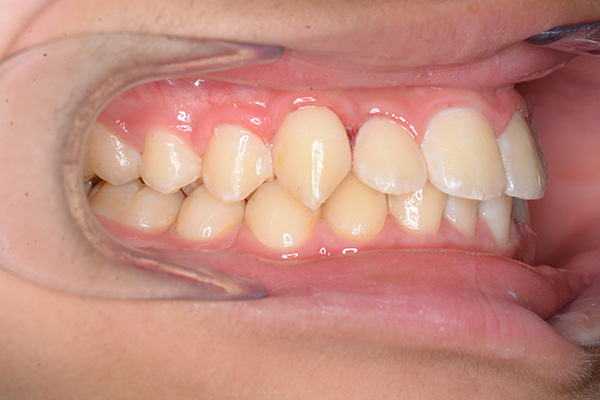

| 口腔内所見 | over jet 5.5mm,over bite 5.0mm,大臼歯関係はⅠ級 、Hellmanのdental ageはⅢBであり上突歯列を呈していた。 |

| セファロ所見 | Sellaに対して下顎頭は後方位だが下顎骨は大きくしっかりとした形態をしており前後的にはⅠ級、垂直的にはロウアングルの骨格形態をしていた。 上顎前歯は唇側傾斜を呈していた。 |

| パノラマ所見 | 上顎左右側犬歯は近心傾斜し側切歯歯根に重なるように認められた。 |

| 批評・予后 | 埋伏歯の牽引を行い位置異常の改善をした結果、適切な犬歯のガイドが得られ、ほぼ緊密な咬合となったように思う。口元の改善を希望された場合は小臼歯抜歯症例として本格矯正治療を行う予定である。 |